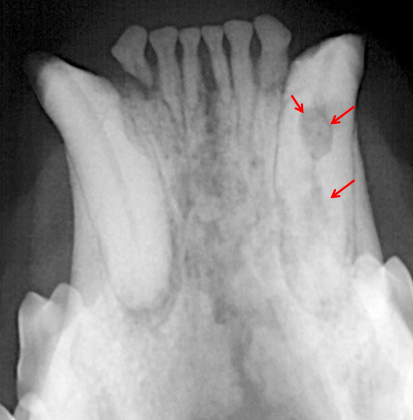

25

DX?

résorption inflammatoire rapide (au stage 2 en ce moment je pense) => a envahit la dentine mais pas la pulpe encore